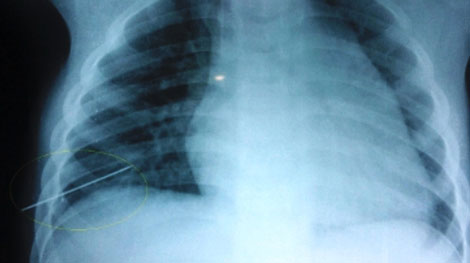

Ngày 3/5, các bác sỹ Bệnh viện Hữu nghị Việt Nam - Cuba Đồng Hới, Quảng Bình cho biết, sức khỏe của cháu Trần Chương Sỹ Cường (3 tuổi), trú xã Hoàn Trạch, huyện Bố Trạch, tỉnh Quảng Bình, đã bình phục tốt.

Mẹ cháu bé dùng kim may quần áo và đánh rơi kim xuống giường ngủ, và không may chiếc kim dài 5cm này đã đâm thấu ngực cháu trong lúc nằm ngủ.